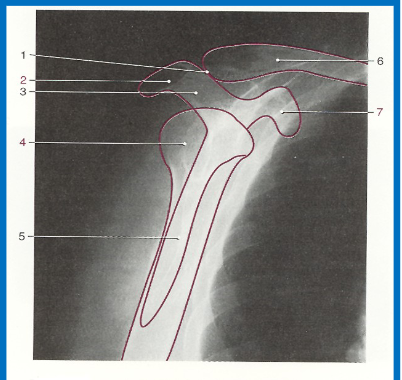

label 1-7 accordingly

1. AC joint

2. Acromion

3. Scapular spine

4. Humeral head

5. Body of scapula (superimposed over

humerus)

6. Clavicle

7. Coracoid process